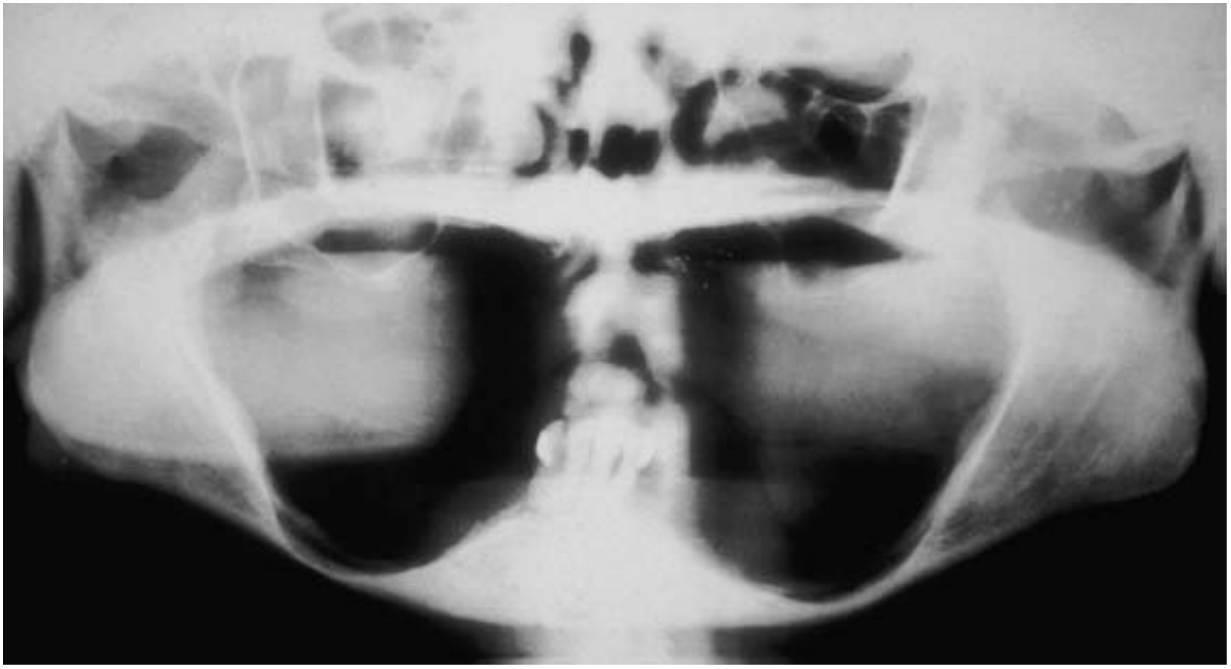

Los huesos necesitan estímulo para mantener su forma y densidad. Roberts y cols, dedujeron que una compresión del 4 % sobre el sistema esquelético mantiene el hueso y ayuda en el equilibrio del fenómeno de reabsorción y formación. Los dientes transmiten las fuerzas de compresión y tensión al hueso circundante. Estas fuerzas se han medido como un efecto piezoeléctrico en los cristales imperfectos de la hidroxiapatita que compone la porción inorgánica del hueso. Al perder un diente, la falta de estimulación en el hueso residual provoca una disminución de la densidad ósea y trabecular en el área, con pérdida del ancho externo, y por tanto de la altura, del volumen óseo. Hay una disminución del 2 5 % en la anchura del hueso durante el primer año posterior a la pérdida del diente y una pérdida de altura toral de 4 mm durante el año siguiente a una extracción en una dentadura inmediata. En un estudio longitudinal de 25 años en pacientes edéntulos, las cefalografías laterales mostraron pérdidas continuas de hueso durante este período de tiempo; se observó una pérdida cuatro veces mayor en la mandíbula65 (fig. 1-14). En cualquier caso, y debido a que la altura mandibular inicial es el doble que la maxilar, la pérdida ósea maxilar también es significativa a largo plazo en el paciente edéntulo.

Un diente es necesario para el desarrollo del hueso alveolar, y se necesita la estimulación de este hueso para mantener su densidad y volumen. Una dentadura removible (parcial o completa) no estimula ni mantiene el hueso; más bien acelera la pérdida ósea. La carga de la masticación se transmite solo a la superficie del hueso, y no a todo el hueso. Como resultado, el aporte sanguíneo disminuye y se produce la pérdida de volumen óseo total. Este asunto, que es de máxima importancia, ha sido observado pero no tratado por la odontología tradicional en el pasado. Los facultativos suelen mirar con indiferencia la pérdida ósea insidiosa que se producirá después de una extracción dentaria. El paciente no suele ser informado acerca de los cambios anatómicos y de las potenciales consecuencias de la continua pérdida ósea. La pérdida ósea se acentúa cuando el paciente lleva una prótesis parcial mucosoportada mal encajada. El paciente no sabe que se va perdiendo hueso en el transcurso del tiempo y a un mayor promedio debajo de una dentadura mal ajustada (fig. 1-15). Los pacientes no vuelven para revisiones regulares para evaluar su estado; en su lugar, vuelven varios años después cuando su dentadura se ha degradado o ya no la pueden tolerar. De ahí que los métodos tradicionales de sustitución de las piezas dentales afecten con frecuencia a la pérdida ósea de una manera no lo suficientemente considerada por el facultativo y el paciente. El facultativo debería informar al paciente de que la dentadura sustituye más al hueso y a los tejidos blandos que a los dientes, y que cada 5 años es conveniente llevar a cabo un rebasado protésico o la colocación de una nueva dentadura para sustituir la pérdida ósea adicional debida a la atrofia (fig. 1-16).

Los rebordes edéntulos atrofiados se asocian a problemas anatómicos que suelen deteriorar los resultados predecibles de las técnicas de odontología tradicionales (fig. 1-17).